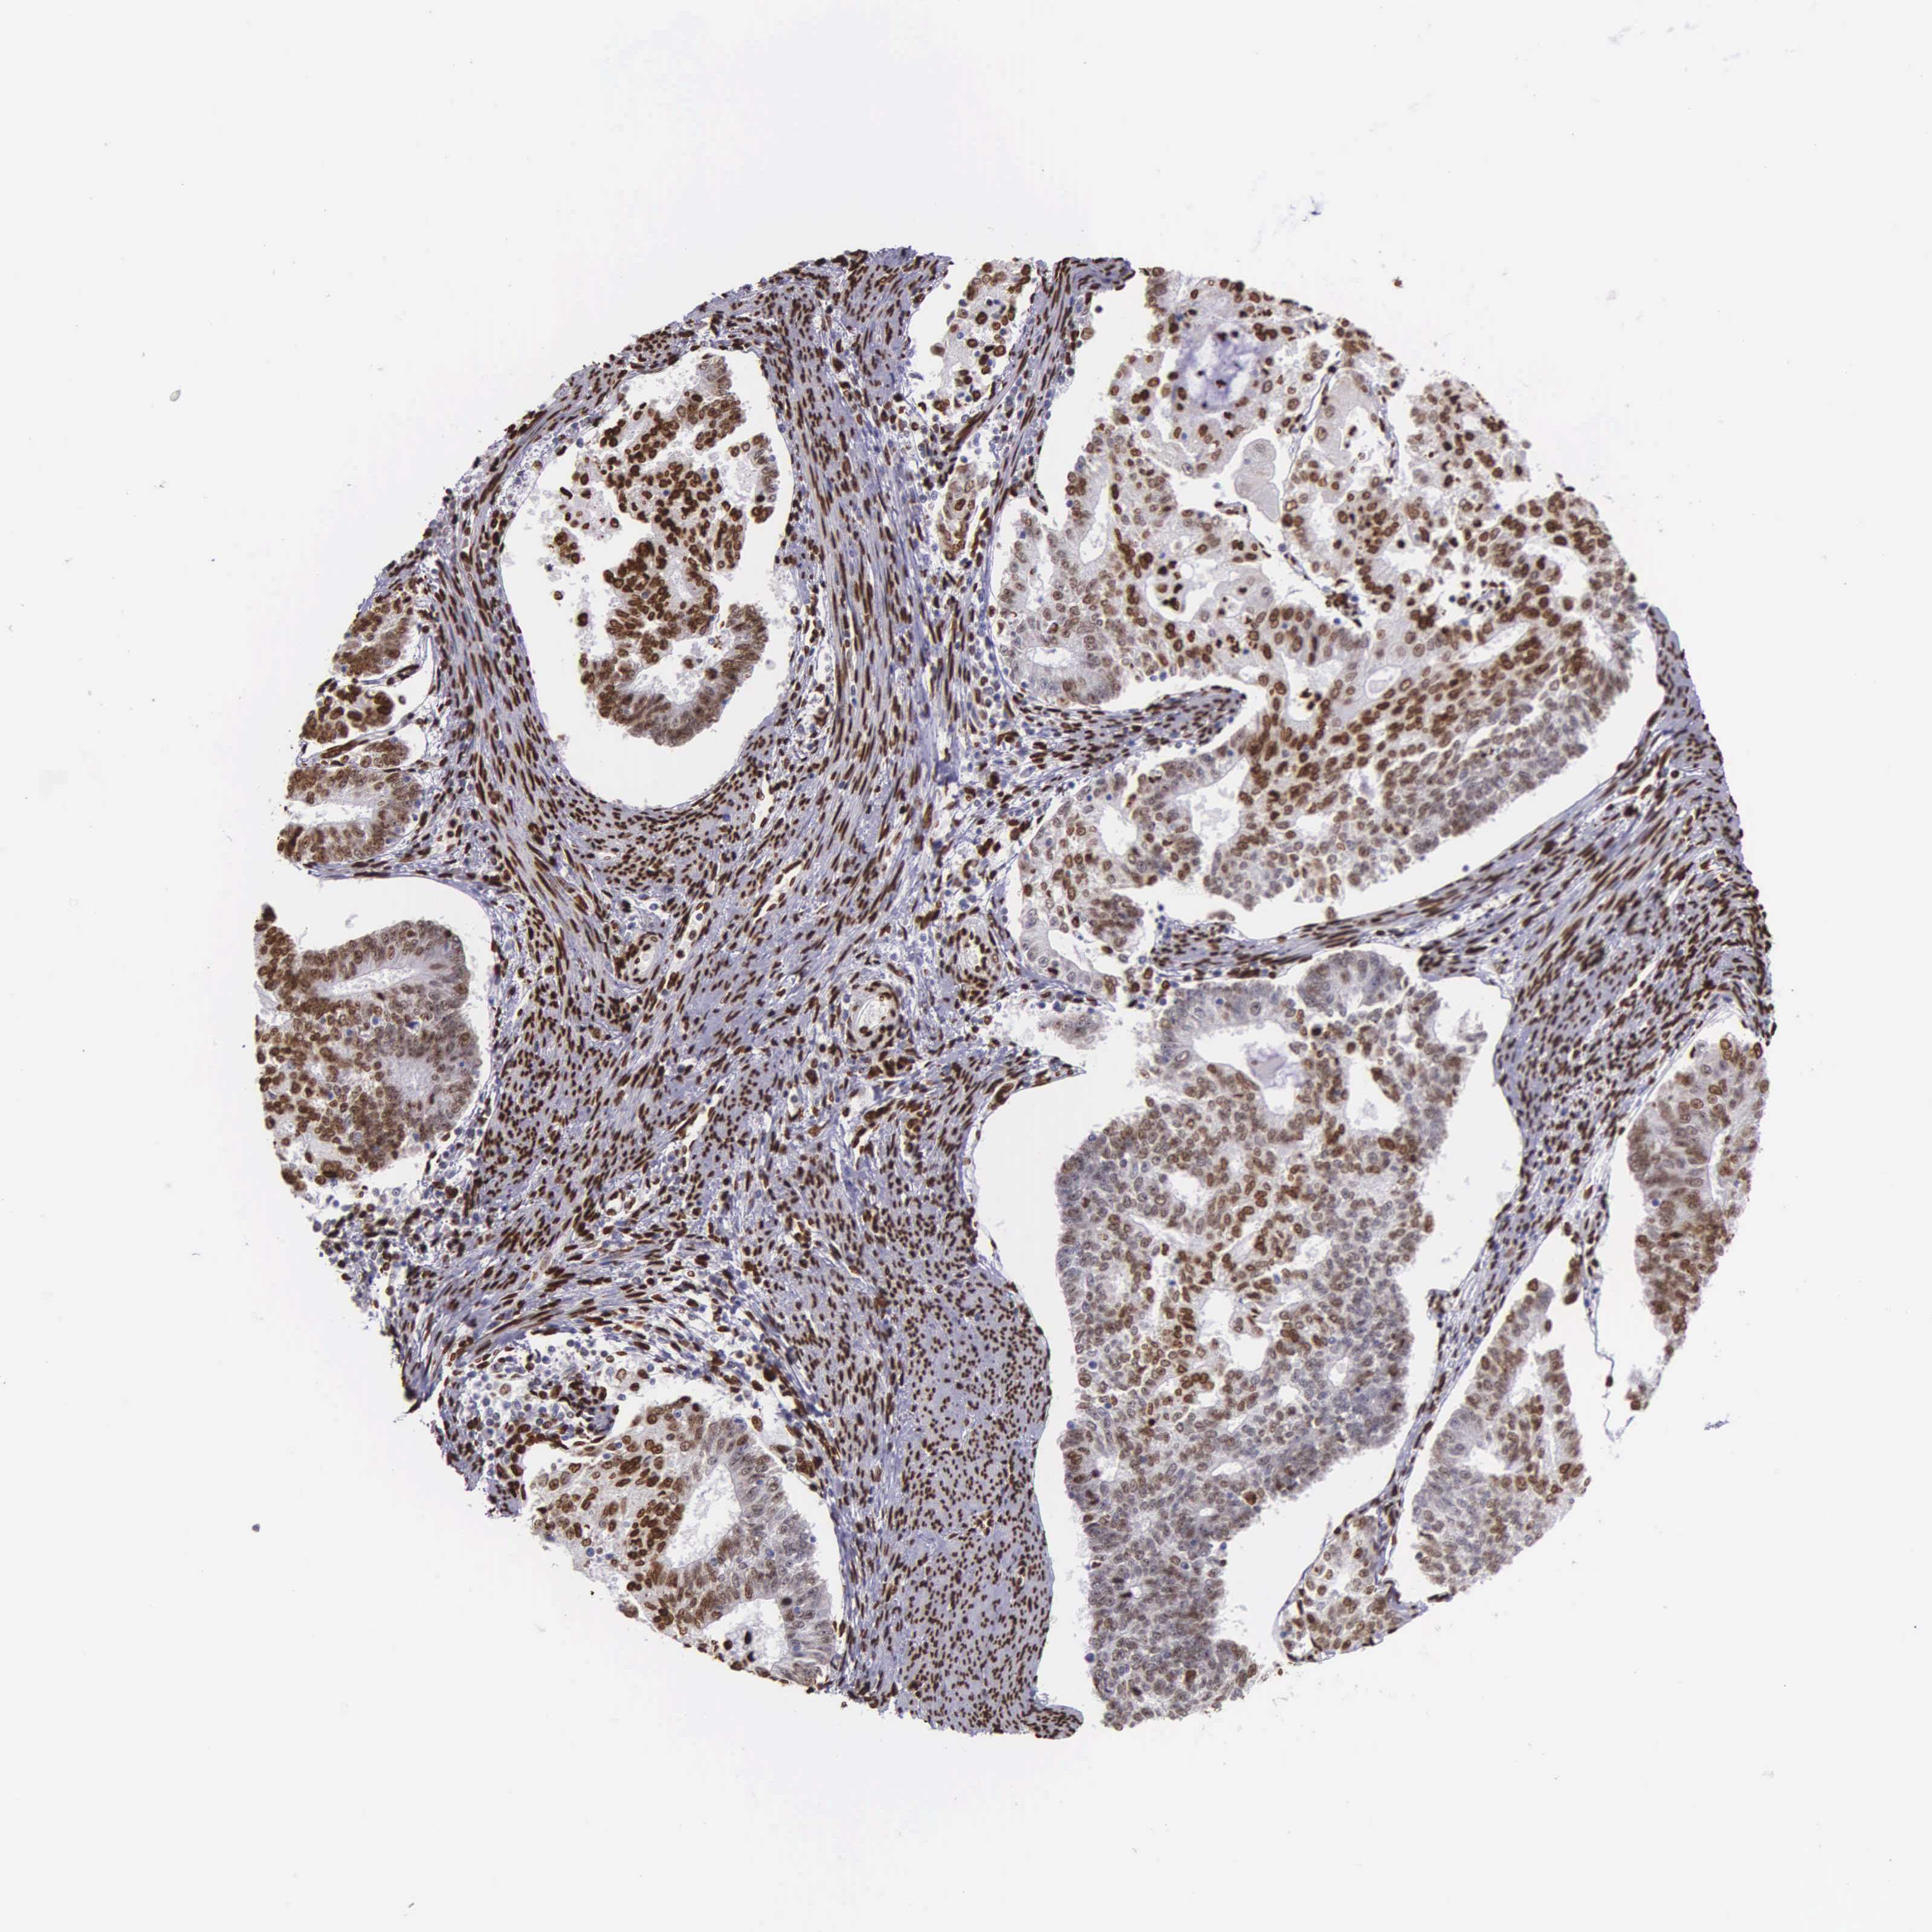

ENDOMETRIAL CANCER - Protein expressioni

A mouse-over function shows sample information and annotation data. Click on an image to view it in a full screen mode. Samples can be filtered based on level of antibody staining by selecting one or several of the following categories: high, medium, low and not detected. The assay and annotation is described here.

Note that samples used for immunohistochemistry by the Human Protein Atlas do not correspond to samples in the TCGA dataset.

Antibody stainingi

Antibody staining in the annotated cell types in the current human tissue is reported as not detected, low, medium, or high, based on conventional immunohistochemistry profiling in selected tissues. This score is based on the combination of the staining intensity and fraction of stained cells.

Each image is clickable and will lead to virtual microscopy that enables deeper exploration of all samples and also displays staining intensity scores, fraction scores and subcellular localization as well as patient and tissue information for each sample.

Antibody HPA000843

Staining

High

Medium

Low

Not detected

Intensity

Strong

Moderate

Weak

Negative

Quantity

>75%

75%-25%

<25%

None

Location

Nuclear

Cytoplasmic/membranous

Cytoplasmic/membranous,nuclear

Adenocarcinoma, NOS